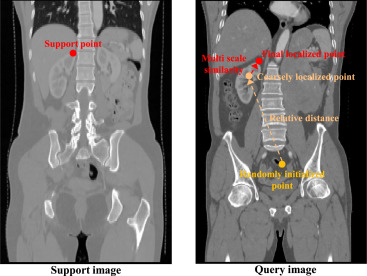

图1. 医学定位任意模型(MedLAM)推理阶段的结构。该过程涉及将一个代理从查询图像中的随机初始化位置向目标地标移动,由3D相对距离和多尺度特征向量引导。